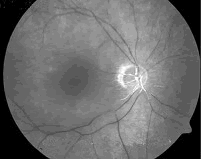

正常人行眼底荧光血管造影检查(如图),臂-视网膜循环时间大约()